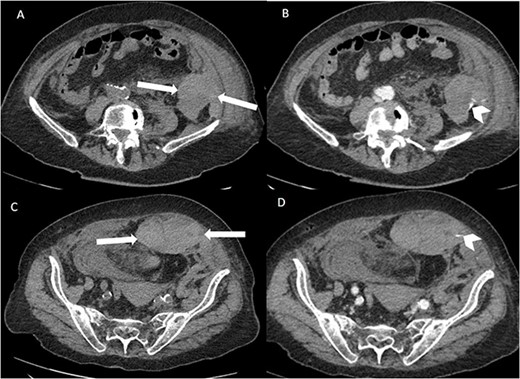

Suspecting internal haemorrhage, contrast-enhanced computed tomography (CECT) of the abdomen and pelvis was arranged. The CT images showed the presence of multiple haematomas with evidence of active bleeding (Figs 1 and 2).

Axial non-contrast and post-contrast (100-s delay) CT abdomen and pelvis slices demonstrating two further left abdominal wall and pre-peritoneal collections (white arrows) with high attenuation on non-contrast slices (A and C) in keeping with haematoma. There is contrast blush in two locations (white chevrons in B and D) in keeping with active bleeding. The vascular territories that have likely contributed to bleeding include branches of left inferior epigastric and left lumbar arteries.